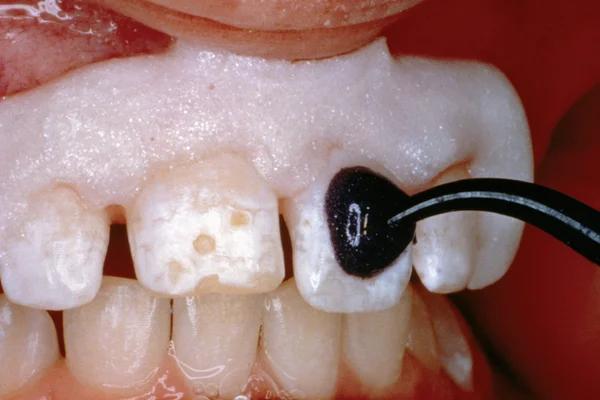

Treatment Protocol: Caries Detection and Preparation

To improve isolation and soft tissue access, a retraction cord was placed before initiating the procedure (Fig. 2). The tooth was evaluated using a caries indicator dye (Kuraray Noritake Dental), helping to identify any remaining infected tissue beneath the dislodged composite (Fig. 3). Decay removal was completed with a diamond bur, and the enamel was bevelled using a starburst pattern to enhance aesthetic blending (Fig. 4). This preparation design was chosen for visual integration rather than bond strength enhancement.

Figure 1. Initial presentation of tooth #6 showing the Class V lesion with dislodged previous restoration and exposed dentin.

Application of caries indicator dye to identify remaining infected tissue beneath the dislodged composite.

Figure

Figure 3.